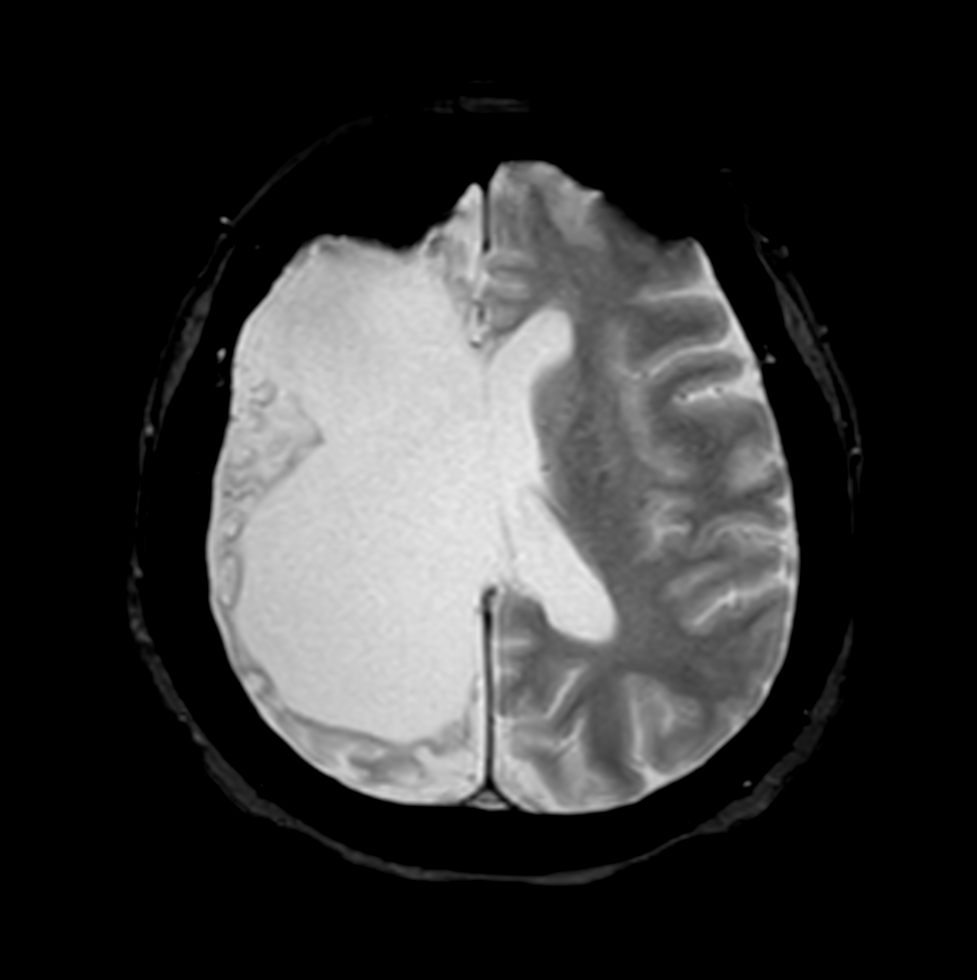

Axial 3D BrainVIEW FLAIR (without Compressed SENSE)

Axial 3D BrainVIEW FLAIR (Compressed SENSE)